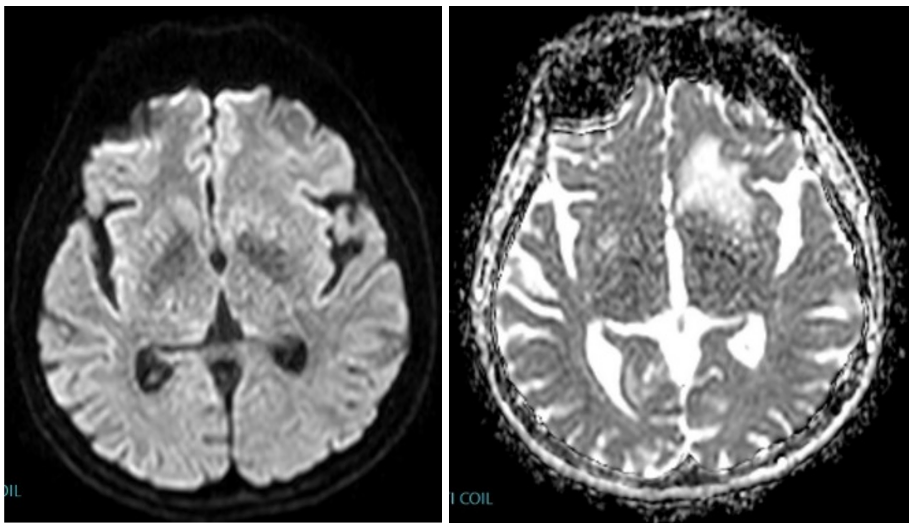

Result of MRI was at T1WI hypointense lesion as seen on (Figure 4), at fluid sensitive sequences T2WI \ FLAIR the lesion is hyperintense as shown in (Figure 5), after GAD enhancement there's irregular ring enhancement of the lesion (Figure 6). Followed by vasogenic edema that is visible in flair sequence at the medial aspect of base of frontal lobe that also affects the head of caudate nucleus. No diffusion restriction was seen in DWI and ADC sequences (Figure7a,7b). In SWI there's no detection of blood products.

Figure 7: Axial(a) DWI and(b) ADC show no restriction in diffusion.